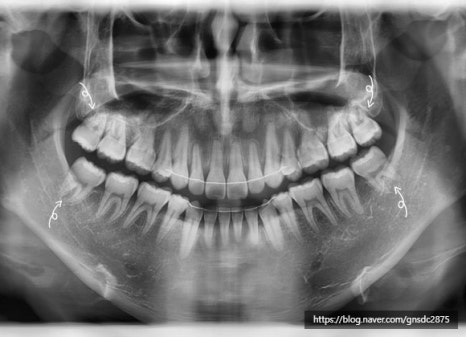

사랑니 통증 방치 사례

다음은 실제 사랑니 통증을 방치하다

뒤늦게 발치를 진행한 사례입니다.

#CASE

사랑니 통증 방치 후

잇몸뼈 소실

해당 환자분은 사랑니쪽의

지속적인 통증을 느껴오셨으나

일이 바빠 약을 먹으며 버티시다

극심한 통증으로

뒤늦게 발치를 진행한 케이스입니다.

상태를 확인해보자

방치된 사랑니 주변 염증으로

옆 어금니의 잇몸뼈가 소실되어

뿌리가 지탱하지 못해 흔들리는 상태였습니다.

빨간색:사랑니 / 파란색:어금니 / 빨간선:소실된 잇몸

겉으로 보기엔 초기충치 정도만 진행되어

신경치료를 진행해 최대한 살리고 싶었지만

사랑니와 함께 옆어금니도 함께 발치하여

어금니는 뼈이식 후 임플란트를 하기로 결정했습니다.